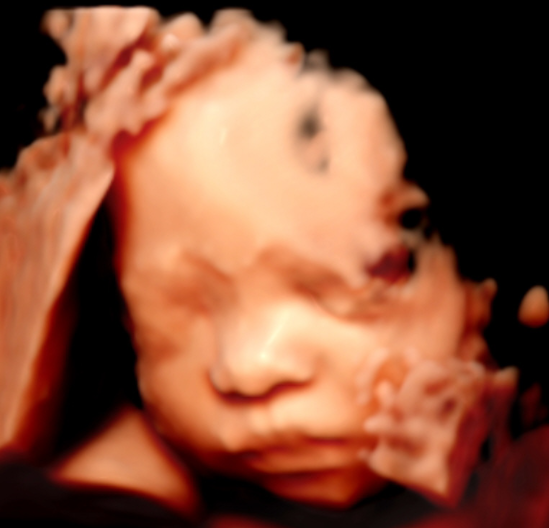

5D智能彩超拥有更高的分辨率和更强的图像处理能力,能够呈现出接近“IMAX电影画质”的细腻影像 。它采用一种被称为“水晶成像”的技术,能够穿透组织,将胎儿的骨骼、器官和组织结构以极其清晰、立体的形态展示出来。这种高清晰度对于观察胎儿微小的解剖结构细节至关重要,例如手指、脚趾、耳廓形态等,有助于医生发现一些在传统超声下不易察觉的细微异常,为排畸诊断提供了更丰富的视觉信息。

4. 温情互动,一次充满感动的“亲子会面”

除了严谨的医学诊断价值,5D彩超也为准爸妈们带来了无与伦比的情感体验。通过高清逼真的动态影像,您可以清晰地看到宝宝的每一个细微表情和动作,仿佛他(她)就在眼前。这份提前到来的“亲密接触”,不仅能极大地缓解孕期的焦虑,更能加深家庭成员与未出世宝宝之间的情感连接,让等待的每一天都充满更具体的幸福感。